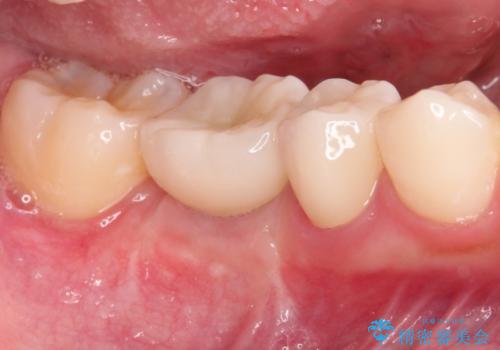

- 右下の奥歯の調子がよくないとのことで来院されました。

レントゲン・口腔内診査をお行い、保存が難しいことがわかりました。

抜歯後インプラントをする計画としました。